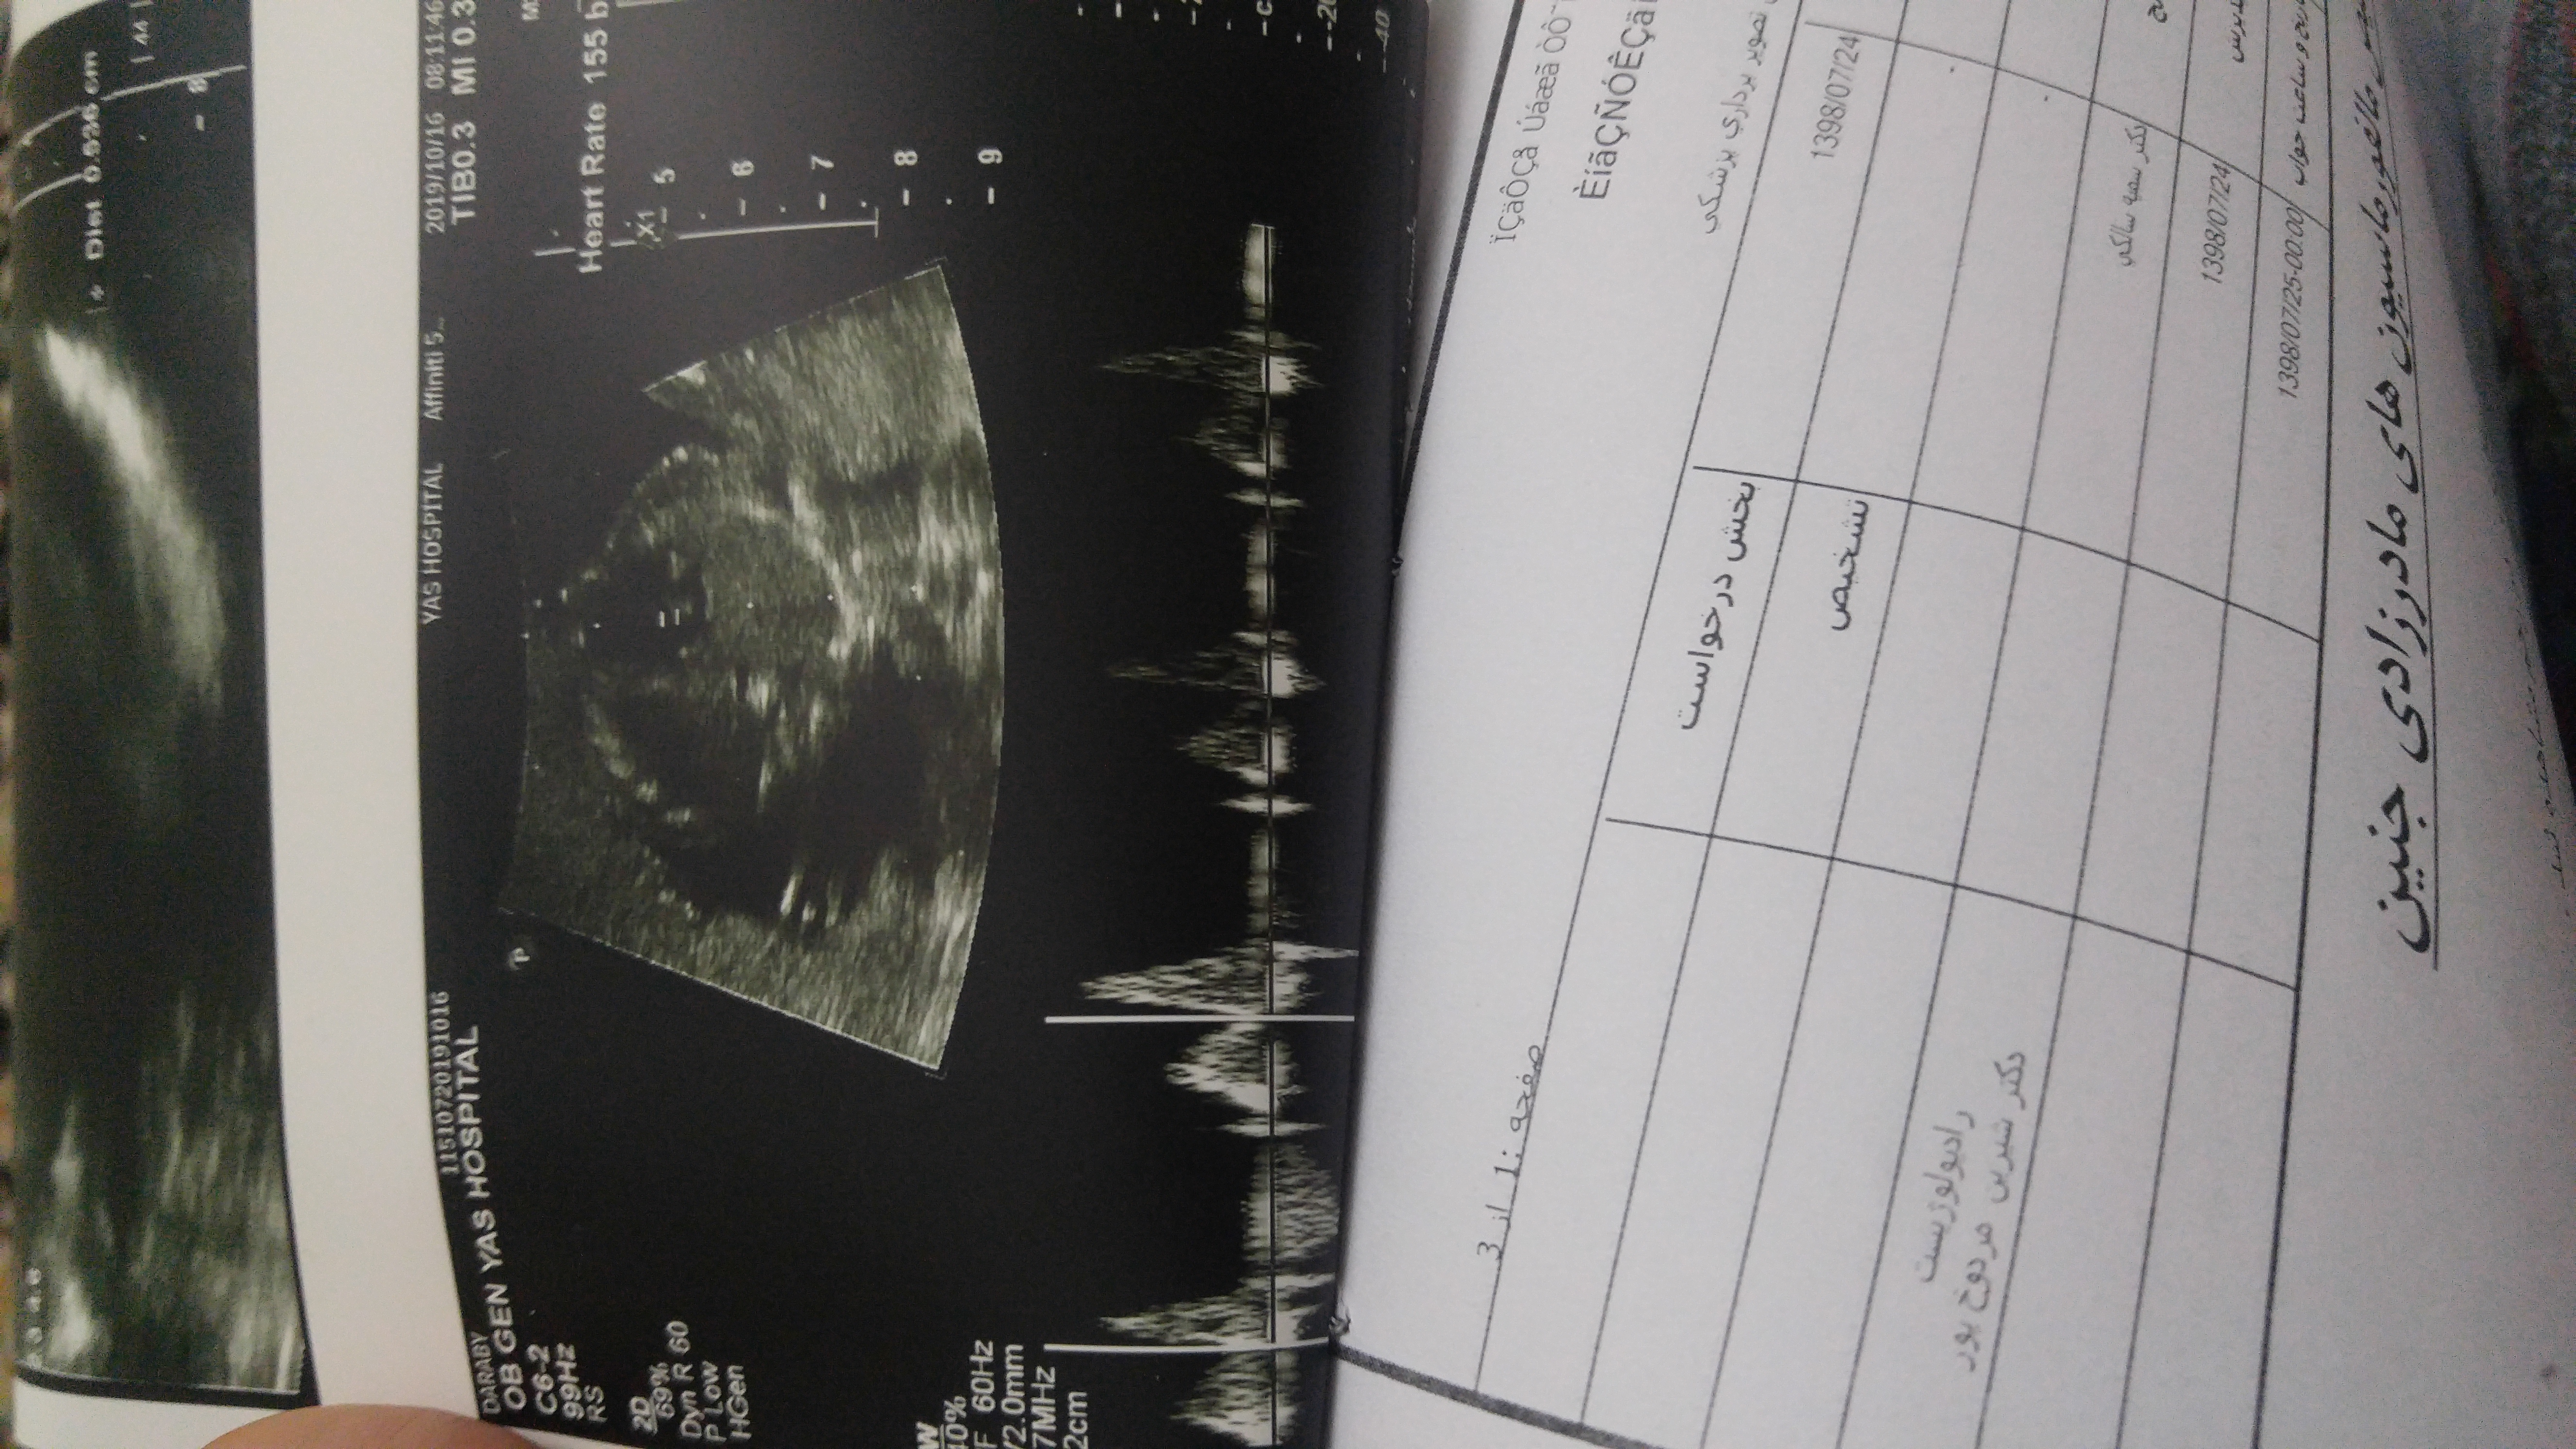

هفته 20 ...4 روز پیش رفتم سونو

نه اصلا عکس واضح ندارم ازش....چندتا دادن نمیدونم چی به چیه

اینابودن نمیدونم اوکی هست یا نه